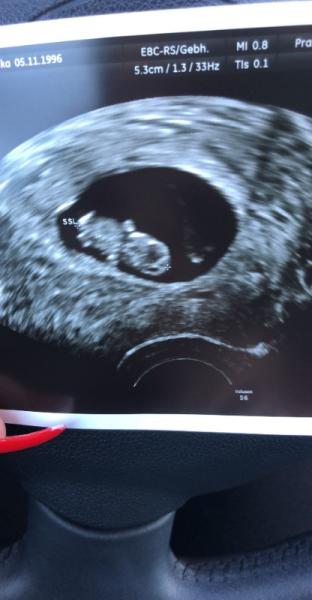

Wir haben heute den 2 Termin gehabt. Der ET wurde auf den 01.01.2020 gelegt. Es ist alles da wo es sein soll und das Herz hat kräftig geschlagen. Ist unser 3 Baby

Bild zu Termin - Forum für Januar - Mamis

Wow da kann man ja schon richtig ein Baby erkennen toll, freue mich für dich. Habe den nächsten US auch in der 10. ssw und freue mich jetzt noch mehr drauf

Ja obwohl es mein drittes Baby sein wird war ich wieder mal erstaunt wie schnell das am Anfang alles geht. Vor 2 Wochen sah man das Baby noch als Punkt wo das Herz flatterte und nun so. Viel Spaß bei deinem nächsten Termin